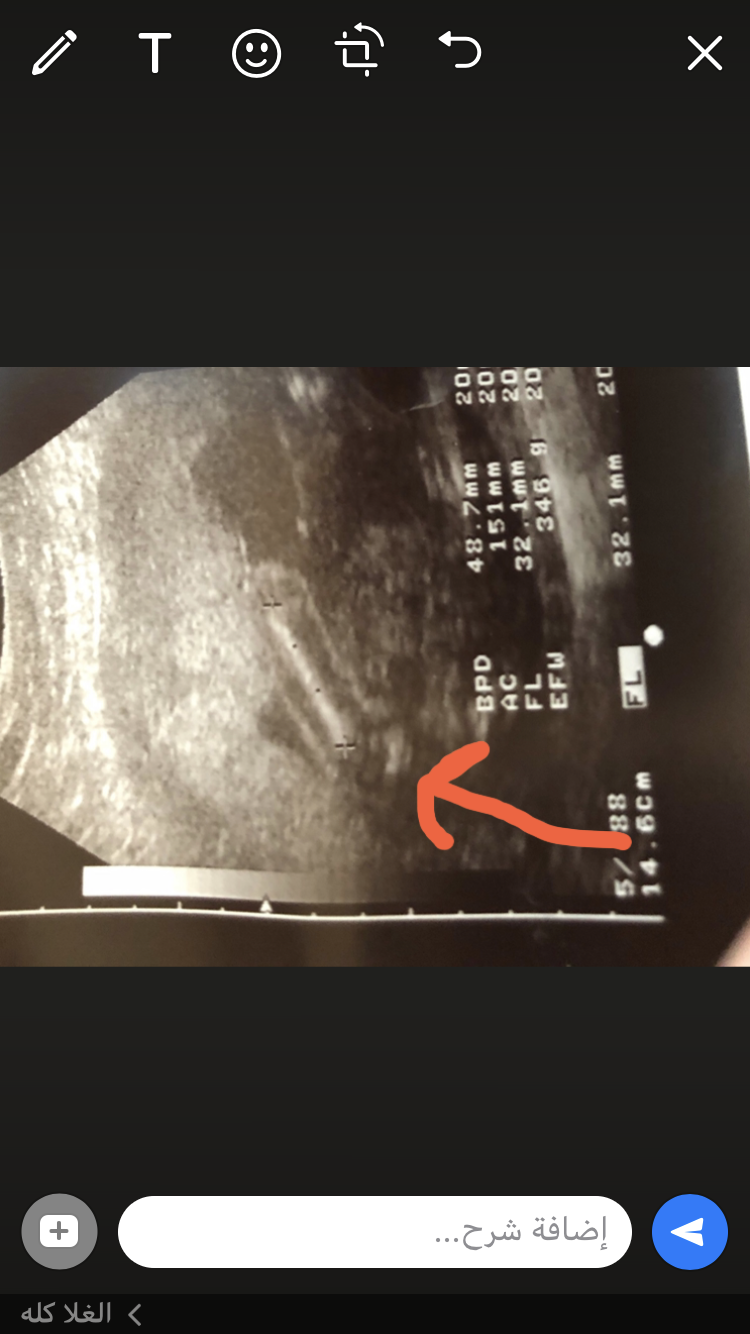

الدكتوره حيرتني في جنس الجنين اول تقول بنت ثم شويات قالت ولد شفت بروز وبتأكد لي بالشهر السادس انتم وش رايكم 🙄🙄🤨

العضو وينه اصلا عشان اعرف

الصوره احسها مو واضحه

الخط الطويل الابيض اللي اخره علامه + هذا الساق